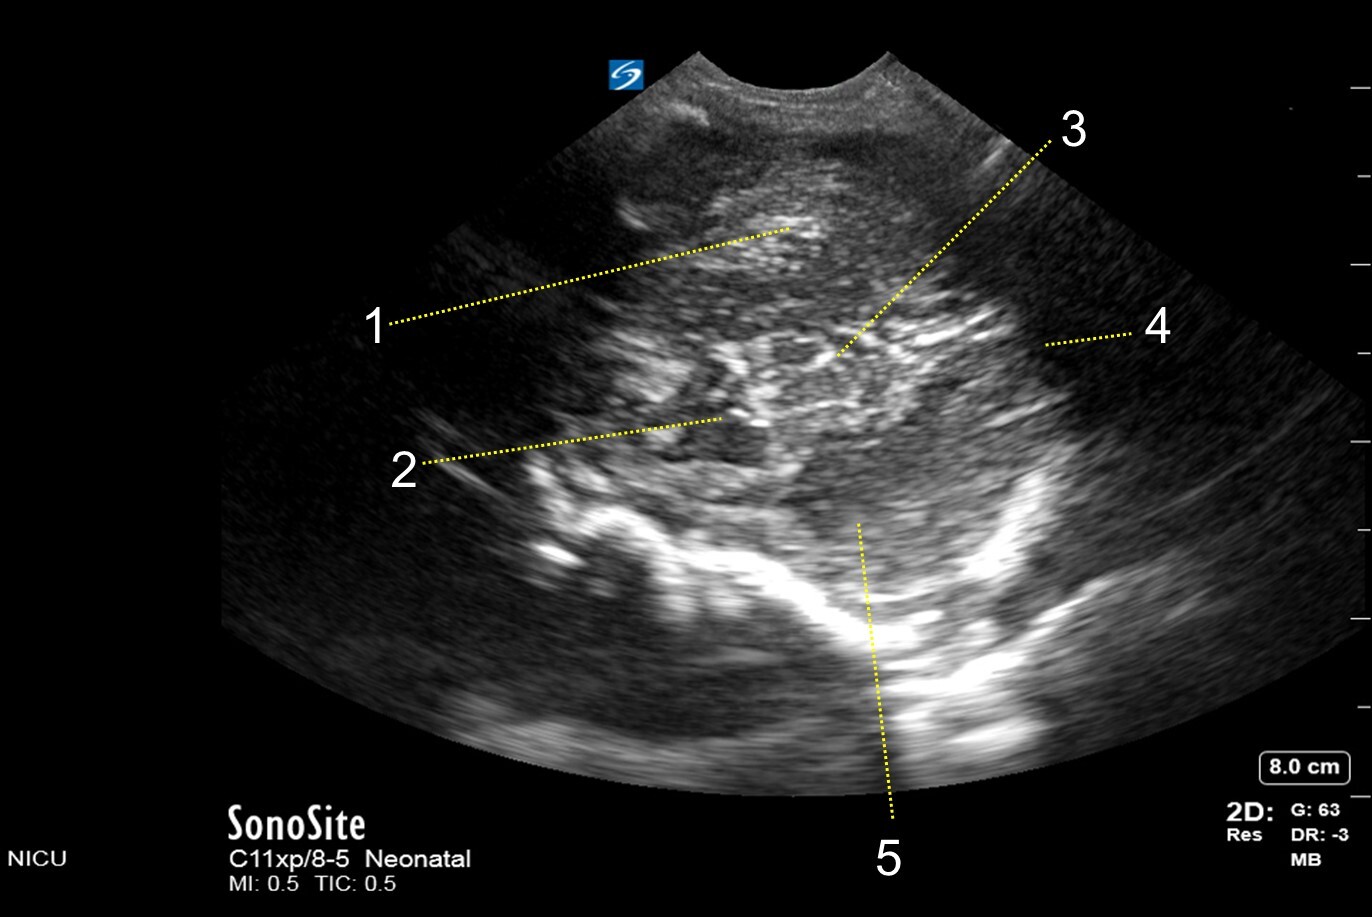

Neonatology Mastoid Fontanel – Inferior Transverse View Image

1. Cerebellar Folia

2. Medulla Oblongata

3. Cerebellum & Vermis

4. Cisterna Magna

5. Cerebellar Hemisphere